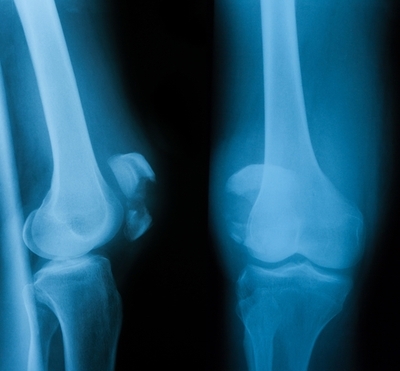

관절염(Arthritis)

관절염은 퇴행성관절염, 류마티스관절염, 외상후 퇴행성관절염으로 구분됩니다. 관절염으로 붓기가 심한 경우에는 양방처치가 반드시 필요합니다. 이 부분은 제 능력으로는 아직 어렵다고 판단됩니다. 다만 관절염으로 진단을 받은 뒤 무릎에 통증만 생기면 관절염 때문이라고 생각하시거나, 사진 찍어보고 관절간격이 좁아져 있으면 통증에 대해 섬세하게 살펴보지 않고 관절염으로 진단을 내리는 경향이 있습니다. 통증은 관절염으로 인해서만 나타나는 것이 아닙니다. 설사 관절간격이 좁아져 있다 해도 붓기가 심하지 않으면 다른 원인으로 인해 통증이 나타났을 경우가 많습니다. 얼마든지 통증 케어가 가능합니다.

치료: 통증의 주된 원인을 찾아 치료하게 됩니다. 대체적으로는 무릎 주변 신경 치료에 집중되고, 대퇴 사두근의 긴장을 풀어주도록 합니다.